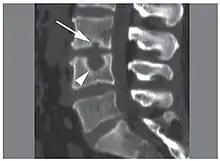

![]() | |

X-ray image of Schmorl's nodes in the lumbar spine | |

Schmorl's nodes can be detected with X-rays, although they can be imaged better by CT or MRI. They are considered to be vertical disc herniations through the cartilaginous vertebral body endplates. Schmorl's nodes can sometimes be seen radiographically, however they are more often seen on MRI, even when not visible on plain X-rays. They may or may not be symptomatic, and their etiological significance for back pain is controversial. In a study in Spine by Hamanishi, et al., Schmorl's nodes were observed on MRI in 19% of 400 patients with back pain, and in only 9% of an asymptomatic control group. The authors concluded that Schmorl's nodes are areas of "vertical disc herniation" through areas of weakness in the endplate.[4]